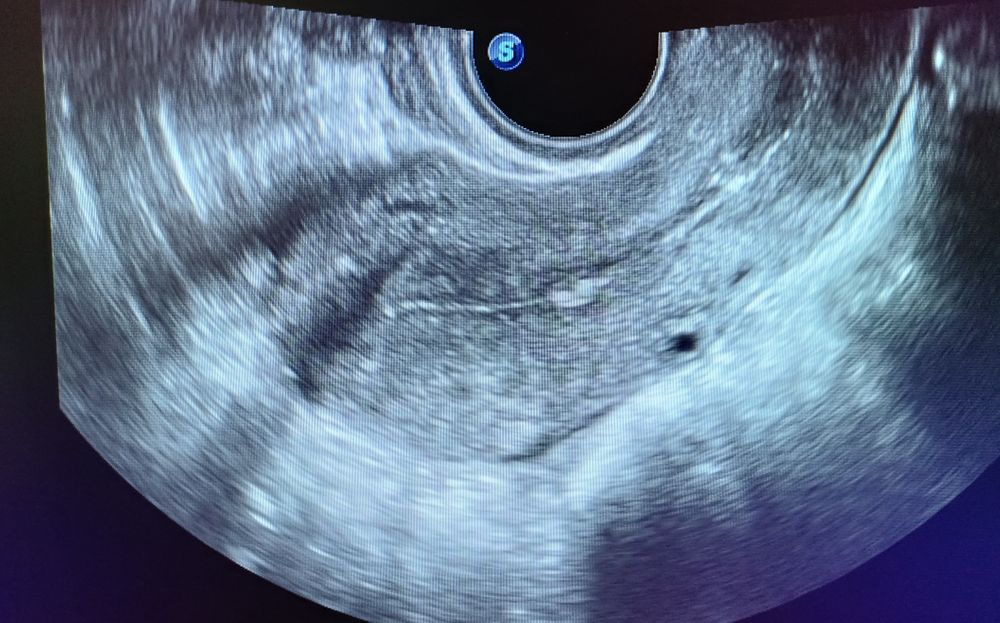

Полип эндометрия.

Здравствуйте. На УЗИ обнаружили признаки полипа эндометрия. Первый раз, в ноябре прошлого года делала УЗИ, все было чисто. Как лечить?